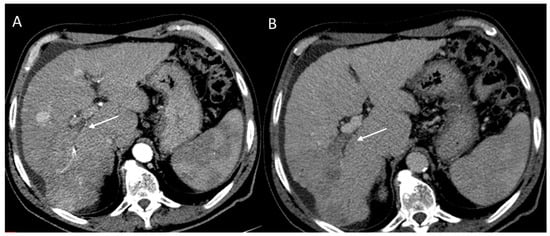

2.2.3. HCC Diagnosis

2.2.5. LR-M Category